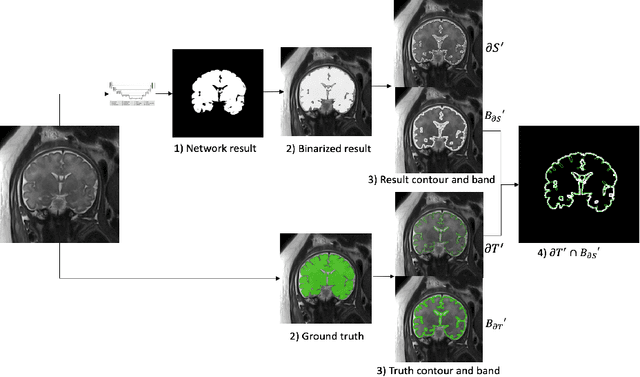

Abstract:Volumetric measurements of fetal structures in MRI are time consuming and error prone and therefore require automatic segmentation. Placenta segmentation and accurate fetal brain segmentation for gyrification assessment are particularly challenging because of the placenta fuzzy boundaries and the fetal brain cortex complex foldings. In this paper, we study the use of the Contour Dice loss for both problems and compare it to other boundary losses and to the combined Dice and Cross-Entropy loss. The loss is computed efficiently for each slice via erosion, dilation and XOR operators. We describe a new formulation of the loss akin to the Contour Dice metric. The combination of the Dice loss and the Contour Dice yielded the best performance for placenta segmentation. For fetal brain segmentation, the best performing loss was the combined Dice with Cross-Entropy loss followed by the Dice with Contour Dice loss, which performed better than other boundary losses.